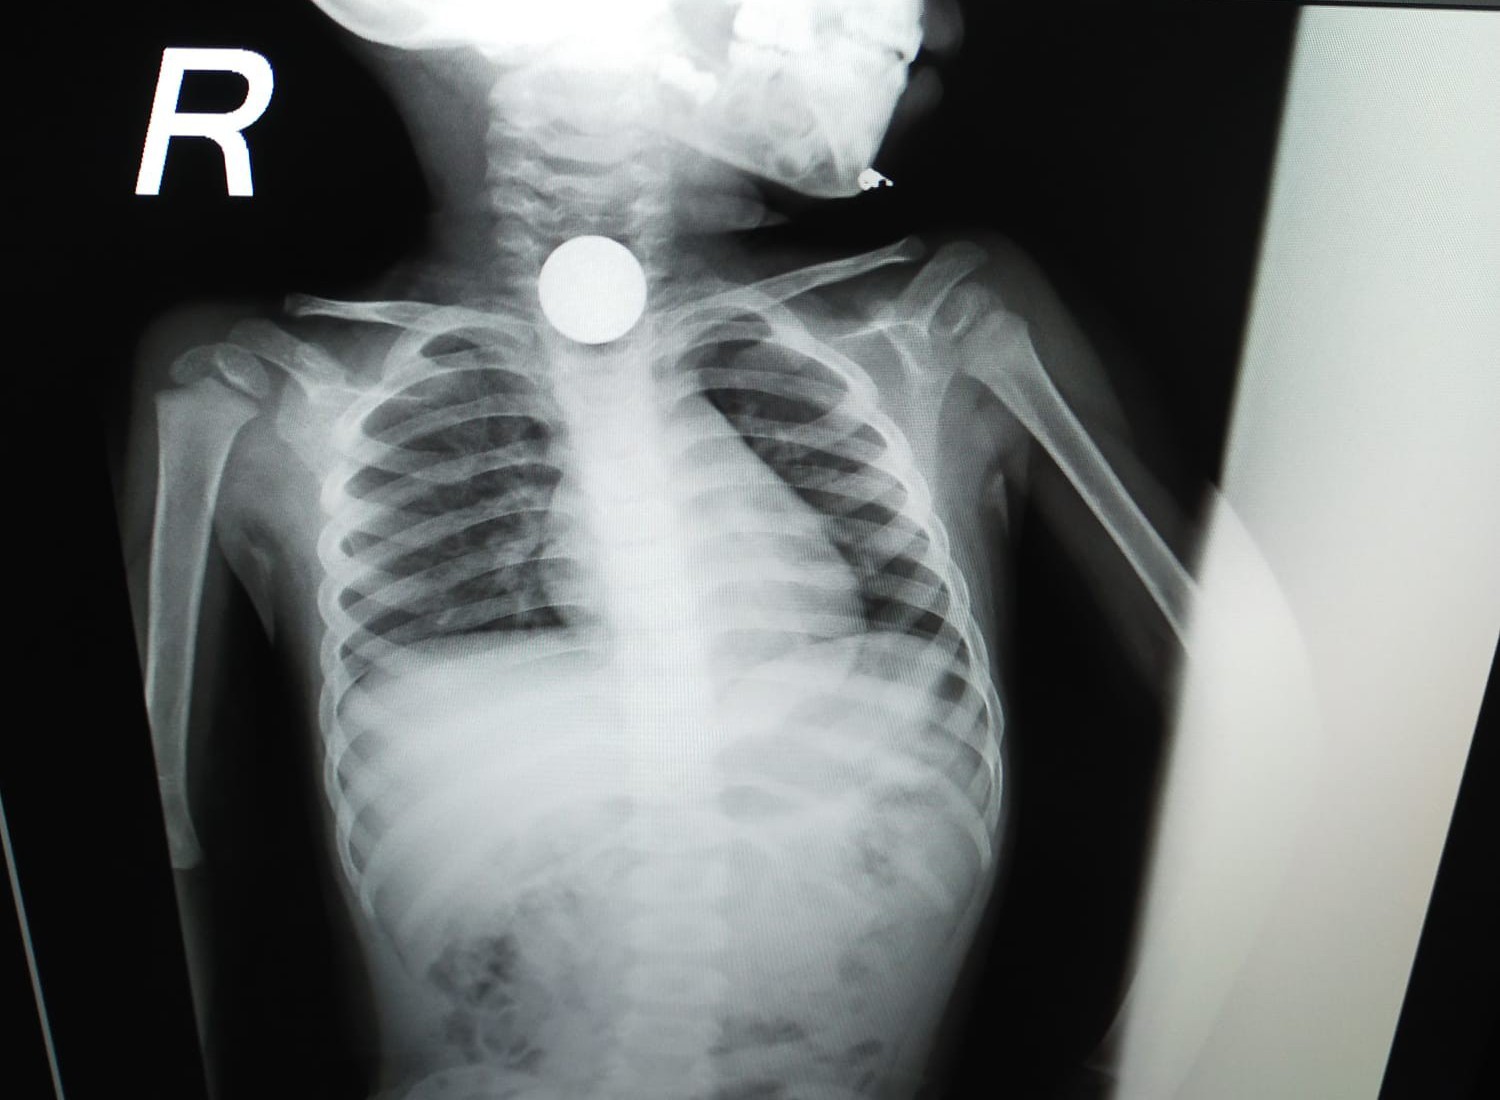

चम्पावत। उत्तराखंड के चम्पावत जिले के टनकपुर निवासी एक 11 वर्षीय बच्चे ने खेलते-खेलते 20 रुपये का सिक्का निगल लिया। जिसे सोमवार देर रात सुशीला तिवारी मेडिकल कॉलेज कॉलेज भर्ती कराया गया। आधी रात में ईएनटी और एनेस्थीसिया विभाग की टीम ने जटिल ऑपरेशन के बाद गले में फंसे सिक्के को निकालकर बच्चे की जान बचाई। जानकारी के अनुसार, टनकपुर के ग्राम मनिहारगोठ निवासी एक दैनिक समाचार पत्र से जुड़े आबिद सिद्दीकी के 11 वर्षीय पुत्र मोहम्मद सैफ ने सोमवार रात आठ बजे घर पर खेलते वक्त गलती से ₹20 रुपये का सिक्का निगल लिया। परिजनों ने उसे टनकपुर संयुक्त अस्पताल में प्राथमिक उपचार कराने के बाद खटीमा के निजी हॉस्पिटल में भर्ती कराया। जहां हालत में सुधार नहीं होने पर परिजन रात करीब एक बजे बच्चे को लेकर सुशीला तिवारी हल्द्वानी पहुंचे।

यहां ईएनटी विभाग के प्रोफेसर डॉ़ शहजाद अहमद की टीम ने बच्चे की जांच की तो सिक्का सांस की नली में फंसा दिखाई दे गया, जिसके बाद ऑपरेशन की तैयारी शुरू हुई इसके बाद प्रोफेसर डॉक्टर शहजाद अहमद की टीम ने आधी रात में लगभग 1:30 बजे गले के अंदर फंसे सिक्के को निकालकर बच्चे की जान बचा ली। उन्होंने बताया कि बच्चे की तबीयत सामान्य होने पर मंगलवार को उसे डिस्चार्ज करके घर भेज दिया गया।